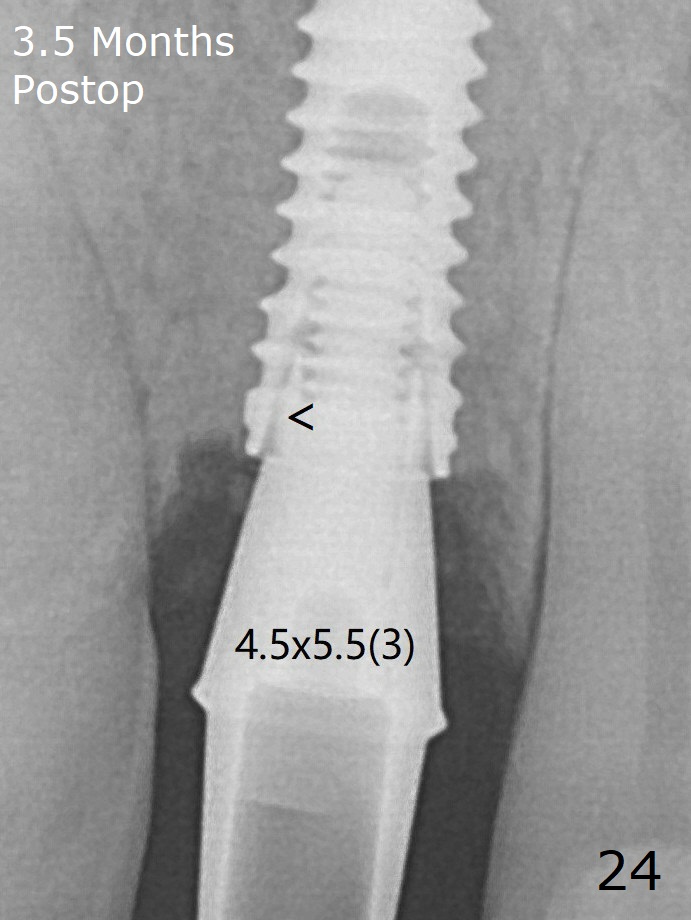

Finally using Lindamann bur, the osteotomy is changed so that a 3.5x13 mm 2-piece implant does not need an angled abutment to establish occlusion (Fig.19). There is one palatal thread exposure. Allograft is placed circumferentially, followed by Human Amnion-Chorion Allograft and Collagen Plug. A 4.5x5.5(3) mm appears to be seated incompletely with a gap between the abutment and the implant (Fig.24 <, overtightened?). A provisional is fabricated after heavy palatal reduction. Two months later, the provisional fractures. After repositioning the abutment with complete seating and torque (Fig.25), impression is taken.